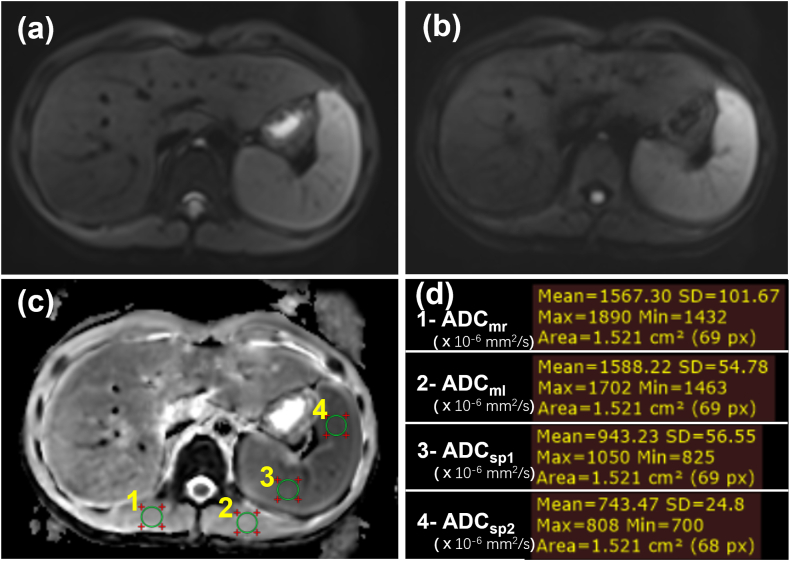

The ADC maps were generated inline during DWI acquisition using a mono-exponential model. ADCspleen and ADCmuscle were measured on a PACS system version 6.0 (GE Healthcare, Milwaukee, WI, USA). Four regions of interest (ROIs) (mean area, 152 ± 3 mm2; range 144–167 mm2) [Fig. 2(a-d)]were drawn within the homogenous parts of the spleen (two ROIs) and the bilateral paraspinal muscles for each patient to measure the ADCspleen and ADCmuscle, which were also used to calculate the normalized ADC including ADCspleen to ADCmuscle ratio (rADCsp/m) and the ADCmuscle to ADCspleen ratio (rADCm/sp). In the repeatability analysis, two DWIs were acquired in the Magnetom Skyra MRI scanner for each of the 73 patients, and average ADCs of twice measurements of the spleen or the paraspinal muscles in each patient were used to evaluate the repeatability of the ADCs and the rADC. In the comparability analysis, the ADCs of bilateral paraspinal muscles and ADCspleen with two different ROIs in each patient were used to evaluate the comparability of the ADCs and the rADC.

Fig. 2.

ADC measurements in the paraspinal muscle and the Spleen. (a) DWI image with b0. (b) DWI image with b800. (c) Four same-size regions of interest (ROIs) for ADC measurements. (d) Results of ADCm and ADCsp measurements. The unit of ADC values is 10−6 mm2/s.

ADC = apparent diffusion coefficient, DWI = diffusion weighted imaging, ADCm = ADC values of the paraspinal muscles, ADCsp = ADC values of the spleen, ADCmr = ADCm in the right paraspinal muscle, ADCml = ADCm in the left paraspinal muscle, ADCsp1 = ADCsp of the first ROI in the spleen, ADCsp2 = ADCsp of the second ROI in the spleen.